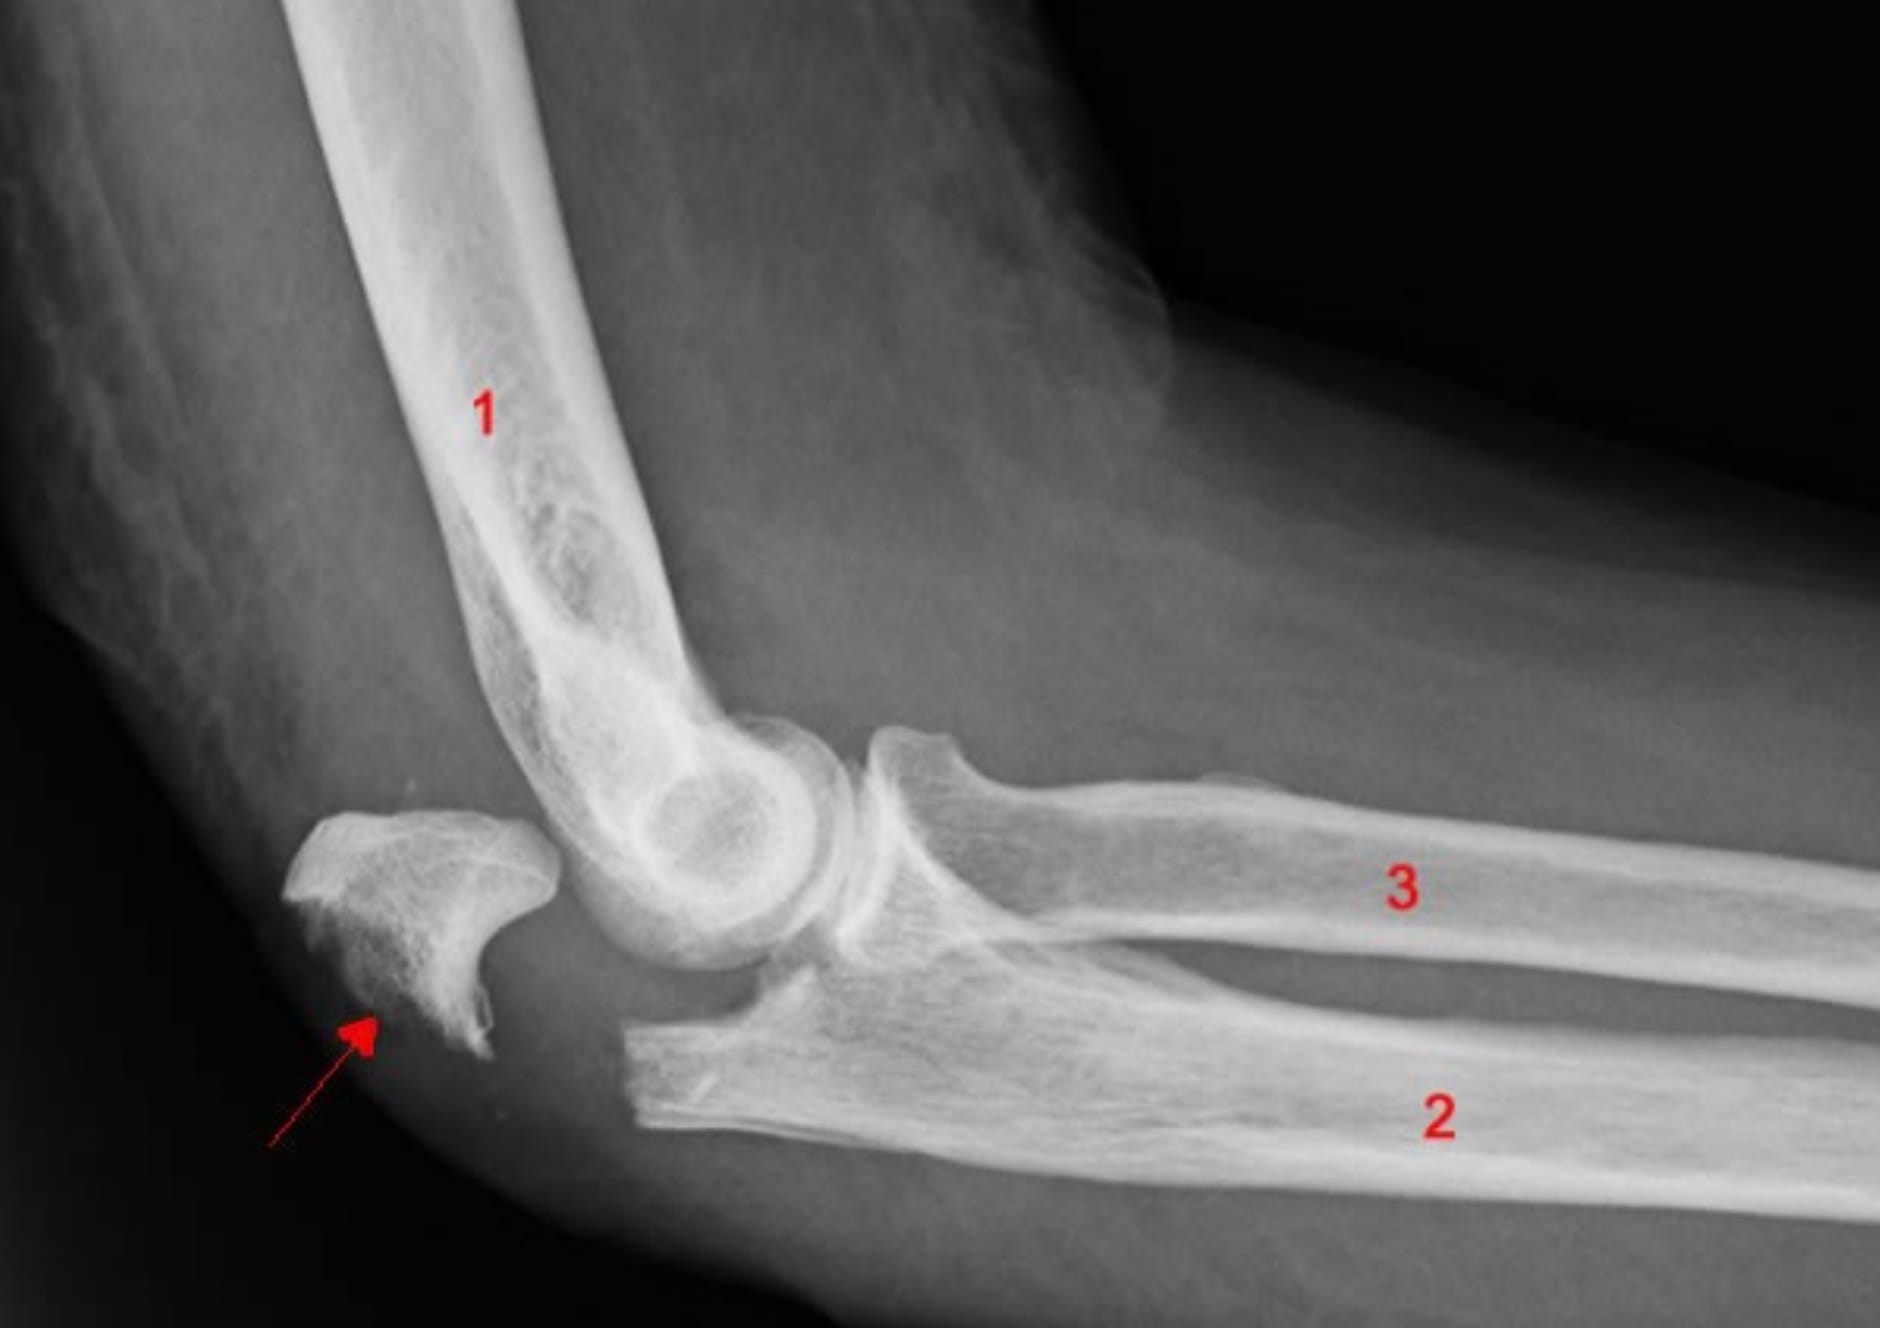

Si la technique ikkyo est alors appliquée martialement, le résultat ressemble à l’image ci-dessous. Il y a fracture de l’olécrane, éventuellement déplacement du radius (3) et du cubitus (2), voire fracture de l’humérus (1) :

Tout ça n’est pas très engageant, mais il faut bien comprendre que la technique ikkyo est faite pour cela, elle n’est pas faite pour amener gentiment un adversaire au sol. Si on amène uke au sol, c’est seulement parce qu’il n’est pas possible évidemment de briser le bras de son partenaire d’entraînement.